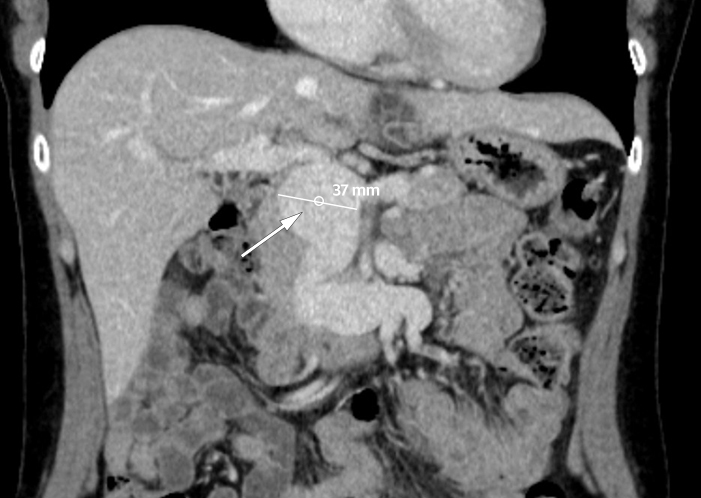

CT-bildet viser et 37 mm stort aneurisme i portvenen, inklusive stammen til vena mesenterica superior og grener til denne. Pasienten var en kvinne i 40-årene med tidligere anoreksi. Hun hadde i fire uker vært plaget av diffuse magesmerter og tidlig metthetsfølelse. Klinisk undersøkelse og orienterende blodprøver hos fastlege, herunder leverprøver, viste normale funn, og hun ble henvist til CT.

Portveneaneurisme er en sjelden tilstand (1). Om lag 200 tilfeller er beskrevet i litteraturen, og kunnskapsgrunnlaget bygger på kasuistikker og pasientserier. Det defineres som en fokal dilatasjon i portvenen, over 15 mm ved normal lever og over 19 mm ved levercirrhose (2–3). Aneurismet er oftest lokalisert til portvenens hovedstamme, dernest ved portvenedelingen (1). Tilstanden kan være medfødt eller ervervet, da oftest grunnet portal hypertensjon sekundært til levercirrhose (1).

Portveneaneurismer oppdages gjerne tilfeldig ved radiologiske undersøkelser eller som ledd i en utredning av magesmerter (1). Hovedparten er asymptomatiske (4). Opp mot 20 % av aneurismene kompliseres av portvenetrombosering (1), men de fleste pasientene utvikler kollaterale blodårer og forblir asymptomatiske (4). Spontanruptur forekommer svært sjelden, trolig fordi venesystemet er et lavtrykksystem (4). Konservativ behandling tilrådes (4). Kirurgi er risikofylt og forbeholdes pasienter der aneurismet vokser raskt, komprimerer nærliggende organer, blør eller er i fare for å rumpere (1). Dersom pasienten ikke har portal hypertensjon, fjerner man aneurismet, mens man ved portal hypertensjon anlegger shunt mellom portvenen og vena cava inferior (1).

Vår pasient hadde ingen underliggende leversykdom, og tilstanden ble oppfattet som medfødt. Hun ble utredet for inflammatorisk tarmsykdom som årsak til magesmertene, men dette ble ikke påvist. Pasienten kontrolleres med regelmessige ultralyd- eller CT-undersøkelser, først etter tre måneder, så hver 6. måned og ved stabile forhold annethvert år.